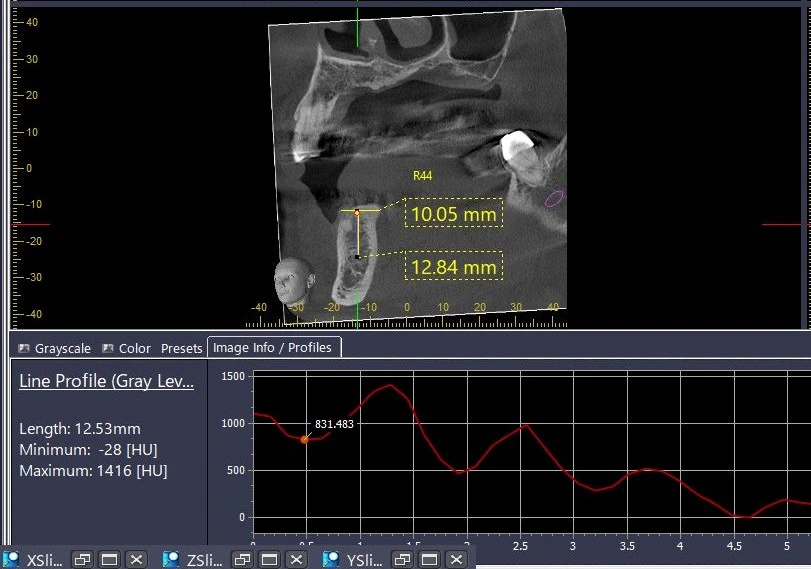

Điều đặc biệt của HU đối với thiết bị CBCT

Ứng dụng của HU trong CBCT rất quan trọng, chẳng hạn, khi khảo sát phim của một Implant mới cấy, đường đồ thị thể hiện chất lượng xương (HU) từ lớp xương vỏ, cắt ngang qua thân Implant có thể dễ dàng cho thấy sự tích hợp của xương quanh thân Implant đó như thế nào.

Tuy vậy, tất cả các CBCT hiện có trên thị trường khi hiển thị chất lượng xương đều không được phép hiển thị là đơn vị HU trừ CBCT của Morita. Các CBCT này chỉ hiển thị chỉ số dưới dạng “Profile”.

Bạn có thể tự mình kiểm chứng điều này khi sử dụng thang đo Profile trên các phần mềm CBCT (hay thang HU trên phần mềm i-Dixel Morita).